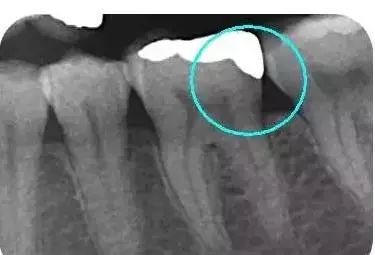

从下面这张X线中可以看出,嵌体远中边缘没有悬突,与牙体边缘密合相接。

这些嵌体,在最终戴入患者口内的时候,真是的非常的完美。在使用上没有任何的影响和不适,而且坚固耐用。